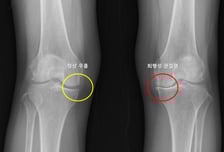

왼쪽 무릎 관절염 환자, 오른쪽도 생길까? 정답 알려주는 '모델' 나왔다

한쪽 무릎에 퇴행성 관절염이 생긴 환자는 다른쪽 무릎에도 똑같은 병이 생기지 않을지 불안에 떨어야 했다. 많은 환자가 한쪽 무릎에 관절염이 생긴 뒤 수년 내 반대쪽 무릎에서도 통증, 구조적 변화가 나타나는 경험을 한다. 하지만 이러한 양측성 진행이 모든 환자에게서 똑같이 나타나지 않아, 이를 예측하려는 연구는 부족했다. 그런데 서울대병원 연구팀이 이런 예측을 가능하게 하는 머신러닝 기반 모델을 개발하는 데 성공했다. 서울대병원 정형외과 노두현 교수팀(김지산 연구원)은 한쪽 무릎에 퇴행성 관절염이 있는 환자들을 대상으로 반대쪽 무릎에서 퇴행성 관절염이 발생할 가능성을 예측하는 머신러닝 모델을 개발했다고 9일 발표했다. 연구는 미국의 대규모 관절염 추적 코호트인 OAI(Osteoarthritis Initiative)와 MOST(Multicenter Osteoarthritis Study) 데이터셋를 기반으로 진행됐으며, 4~5년간 추적 관찰된 편측 무릎 퇴행성 관절염 환자 1353명을